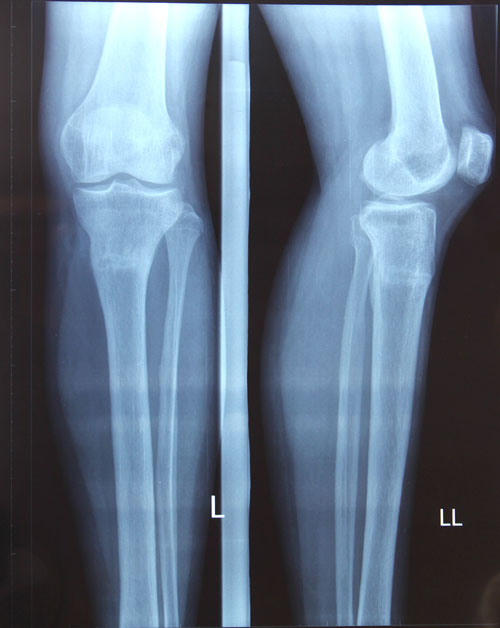

рентген контроль в 1,5 месяца после снятия аппарата.

По результату рентгена - Вам разрешено всё без ограничений (спорт, каблуки, нагрузки). Кроме: беременности в течении первых 6 месяцев после снятия аппаратов.